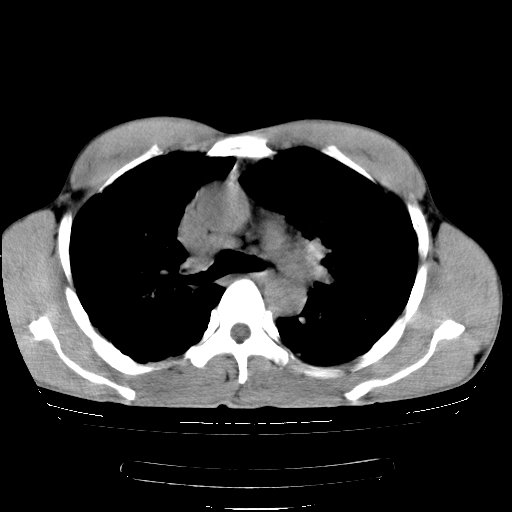

以下是引用yangyudong333在2008-4-29 5:38:00的发言:[br]比较典型的矽肺结节.支持[br]诊断依据:[br] 1.x线表现:[br] ①典型矽肺为多发直径 1~3mm 小结节,即矽结节,由胶原纤维和硅尘构成,可融合成团块,好发于上肺。[br] ②团块周围常有肺大泡。[br] ③胸内淋巴结增大、钙化。如肺门淋巴结呈蛋壳样钙化有助于与其他尘肺区别。[br] ④胸膜常广泛粘连、增厚。[br] 2.ct表现[br] ①两肺散在大小较为一致的小结节影,其密度较高,边界清楚。[br] ②小结节可融合为较大团块影,直径约 1cm ,甚至可达 10cm以上,易发生在上叶。[br] ③小结节周围常并有小叶中心气肿或弥漫性肺气肿。

以下是引用liuyue在2008-4-28 22:30:00的发言:[br]比较典型的矽肺结节.[br]请结合临床及化验除外矽肺合并肺结核之可能.